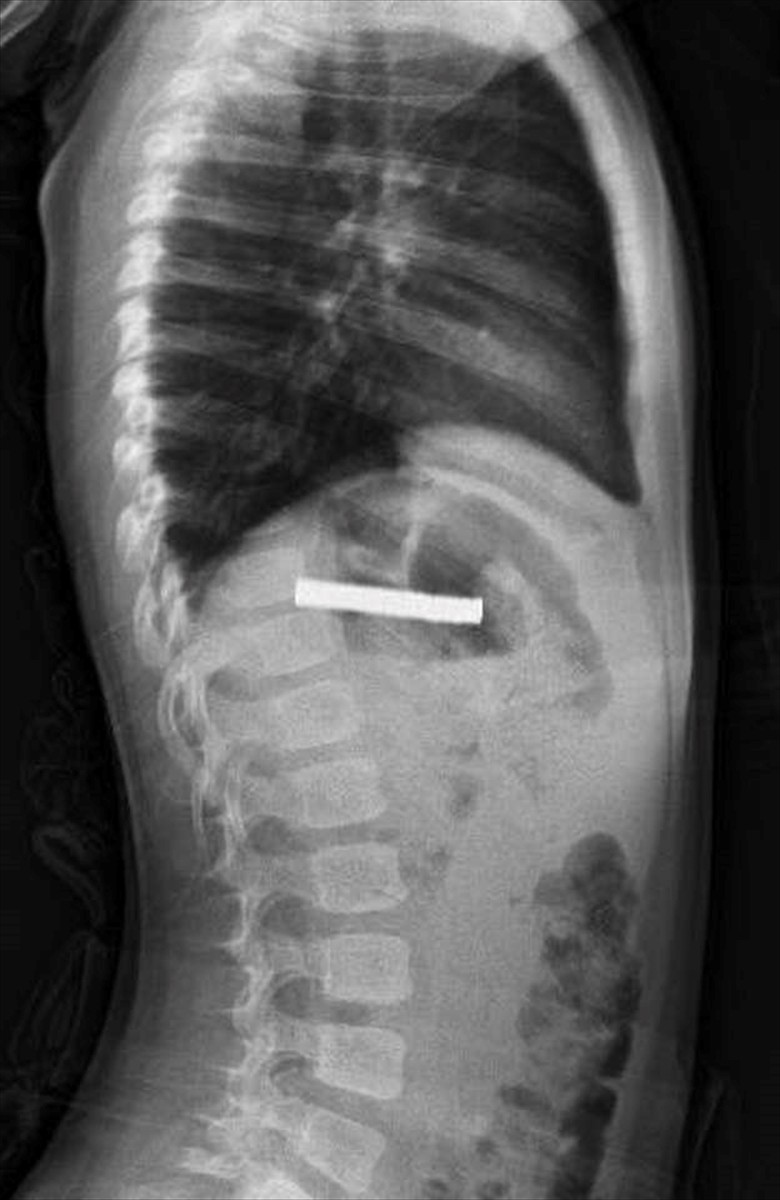

Fırat Üniversitesi Çocuk Gastroenteroloji, Hepatoloji ve Beslenme Bilim Dalı Başkanı Prof. Dr. Yaşar Doğan, çocuğun yemek borusundaki mıknatısların birbirine yapışarak tıkanıklığa neden olduğunu belirledi. Prof. Dr. Doğan ve ekibi, mıknatısların güvenli bir şekilde çıkarılması için bir operasyon gerçekleştirdi.

Prof. Dr. Doğan, "Mıknatıslar uzun süre yemek borusunda kaldığı için hafif bir hasar vermişti. Ancak işlemin kolaylaştırılması için mıknatıslar önce mideye alındı ve oradan özel bir fileyle çıkarıldı. Operasyon sonrası çocuğu gece boyunca gözlem altında tutmayı tercih ettik. Aile sabah kendi isteğiyle taburcu olmak istedi, ve genel durumu iyi olduğu için onu gönderdik," şeklinde konuştu.